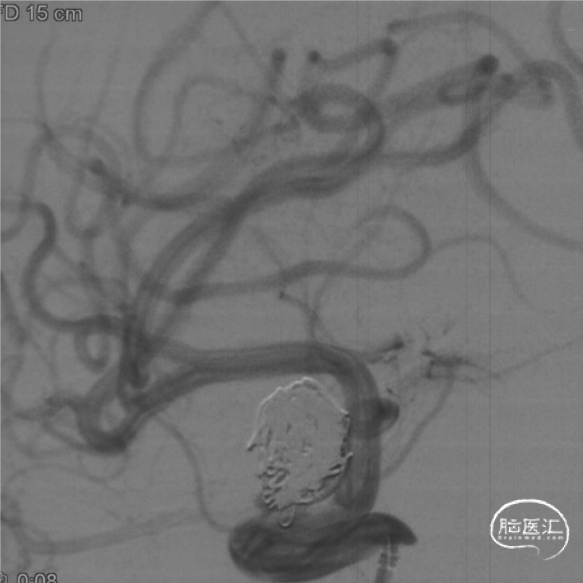

SL-10塑形后填入Target 16/50,14/50两枚弹簧圈。

撤掉SL-10微导管后XT-27微导管置于大脑中动脉。

选择Evolve 4.5/20,输送到位,通过推拉结合方式释放。

支架远端定位于脉络膜前动脉以近,近端位于海绵窦段。

动脉瘤大部栓塞,瘤颈部造影剂滞留。

Vaso CT重建 支架打开、贴壁良好。